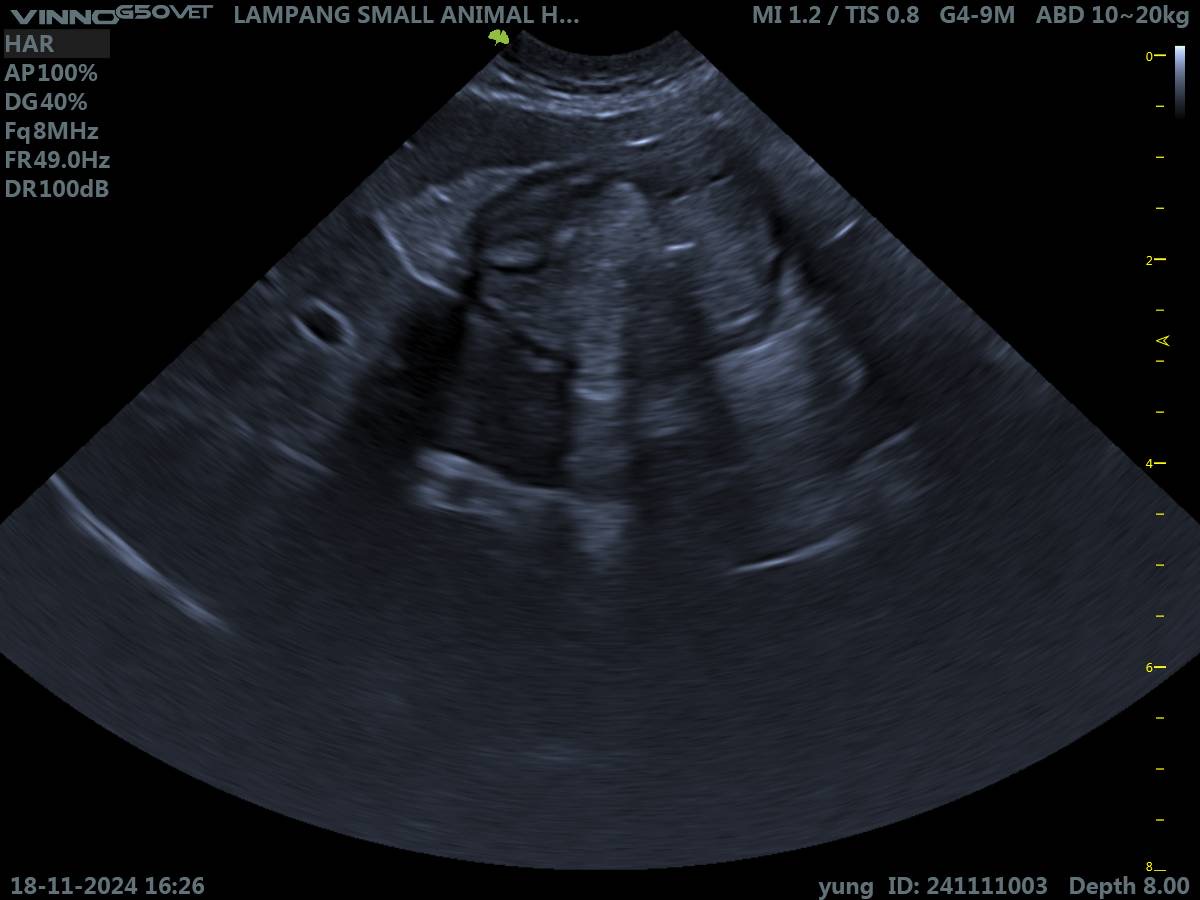

ลักษณะของอาหารที่อาเจียนออกมายังเป็นรูปทรงอยู่ เหมือนน่าจะยังไม่ได้ย่อยค่ะ กินข้าวสัก 10-15 นาทีอาเจียนออกมาแล้ว แต่กินอาหารได้ปกตินะคะ ส่วนการขับถ่ายเนื่องจากเลี้ยงระบบปล่อยเลยไม่เห็นน้องขับถ่ายเลยค่ะเพราะมักจะไปทำธุระกันข้างนอก น้องเคยกินยาจำพวก ลดอาเจียน, ลดกรดในกระเพาะ, เคลือบกระเพาะ มาแล้ว แต่ก็ยังไม่ดีขึ้นค่ะ เคยไปเอกซเรย์คุณหมอบอกไม่มีปัญหาอะไร ส่วนอัลตราซาวด์คร่าว ๆ ว่ามีแผลในกระเพาะอาหารจนเห็นเป็นพังผืดในกระเพาะค่ะ ทำได้แต่ให้ยาไปเรื่อย ๆ แต่ก็ยังไม่ดีขึ้นค่ะ น้องกินยาไปแล้วอ้วกออกมากับอาหารบ้างก็มี เดี๋ยวนี้ช่วงนอนน้องจะครางหนักมากด้วยค่ะ ขออนุญาตส่งผลอัลตราซาวด์ให้ผู้มีความรู้ด้านนี้พิจารณาหน่อยนะคะ ว่าสามารถมีแนวทางการรักษาได้อย่างไรบ้าง ผ่าตัดได้ไหม หรือฉีดยาอะไรได้บ้างไหม ขอบคุณค่ะ🙇🏻♀️ เพื่อน ๆ คนอื่นก็สามารถแสดงความคิดเห็นได้เลยค่ะ เผื่อน้องหมามีอาการคล้าย ๆ กันจะได้มาแชร์กันค่ะ🥹